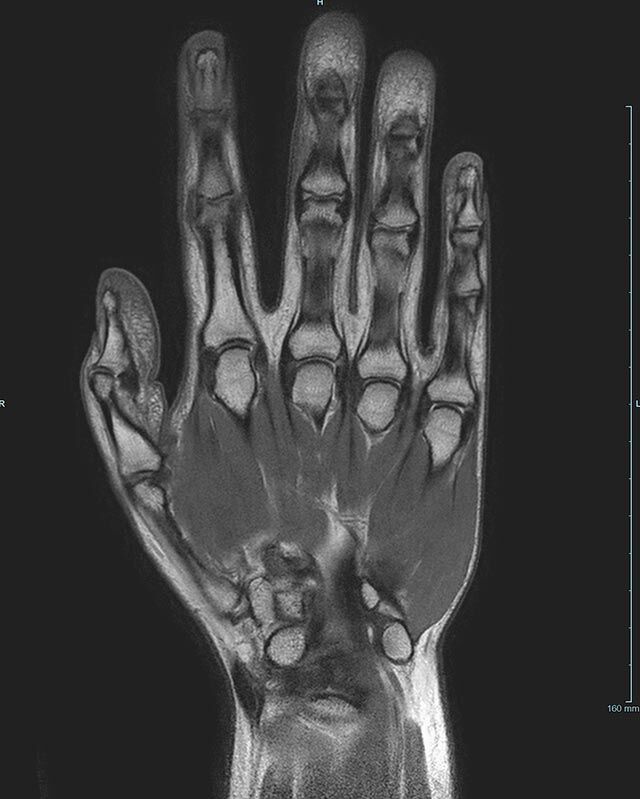

Gelenke

• Beurteilung von Knochen, Bändern und anderen Weichteilstrukturen der Gelenke nach Unfall.

• Arthrosediagnostik (Knorpelschaden)

• Impingement-Symptomatik

• Ursachenklärung bei wiederholter spontaner Gelenkluxation

• Ausbreitungsdiagnostik bei Gelenkentzündung, z.B. im Rahmen von rheumatischen Grunderkrankungen